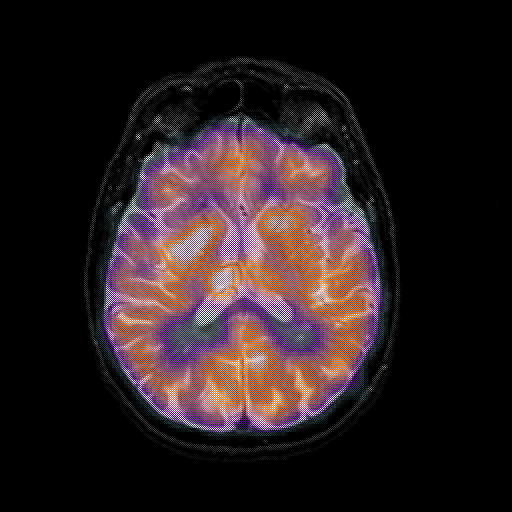

overlay 1: Slice 30

Slice 30

MRCBFCBF with

T1PDT2T1PDT2